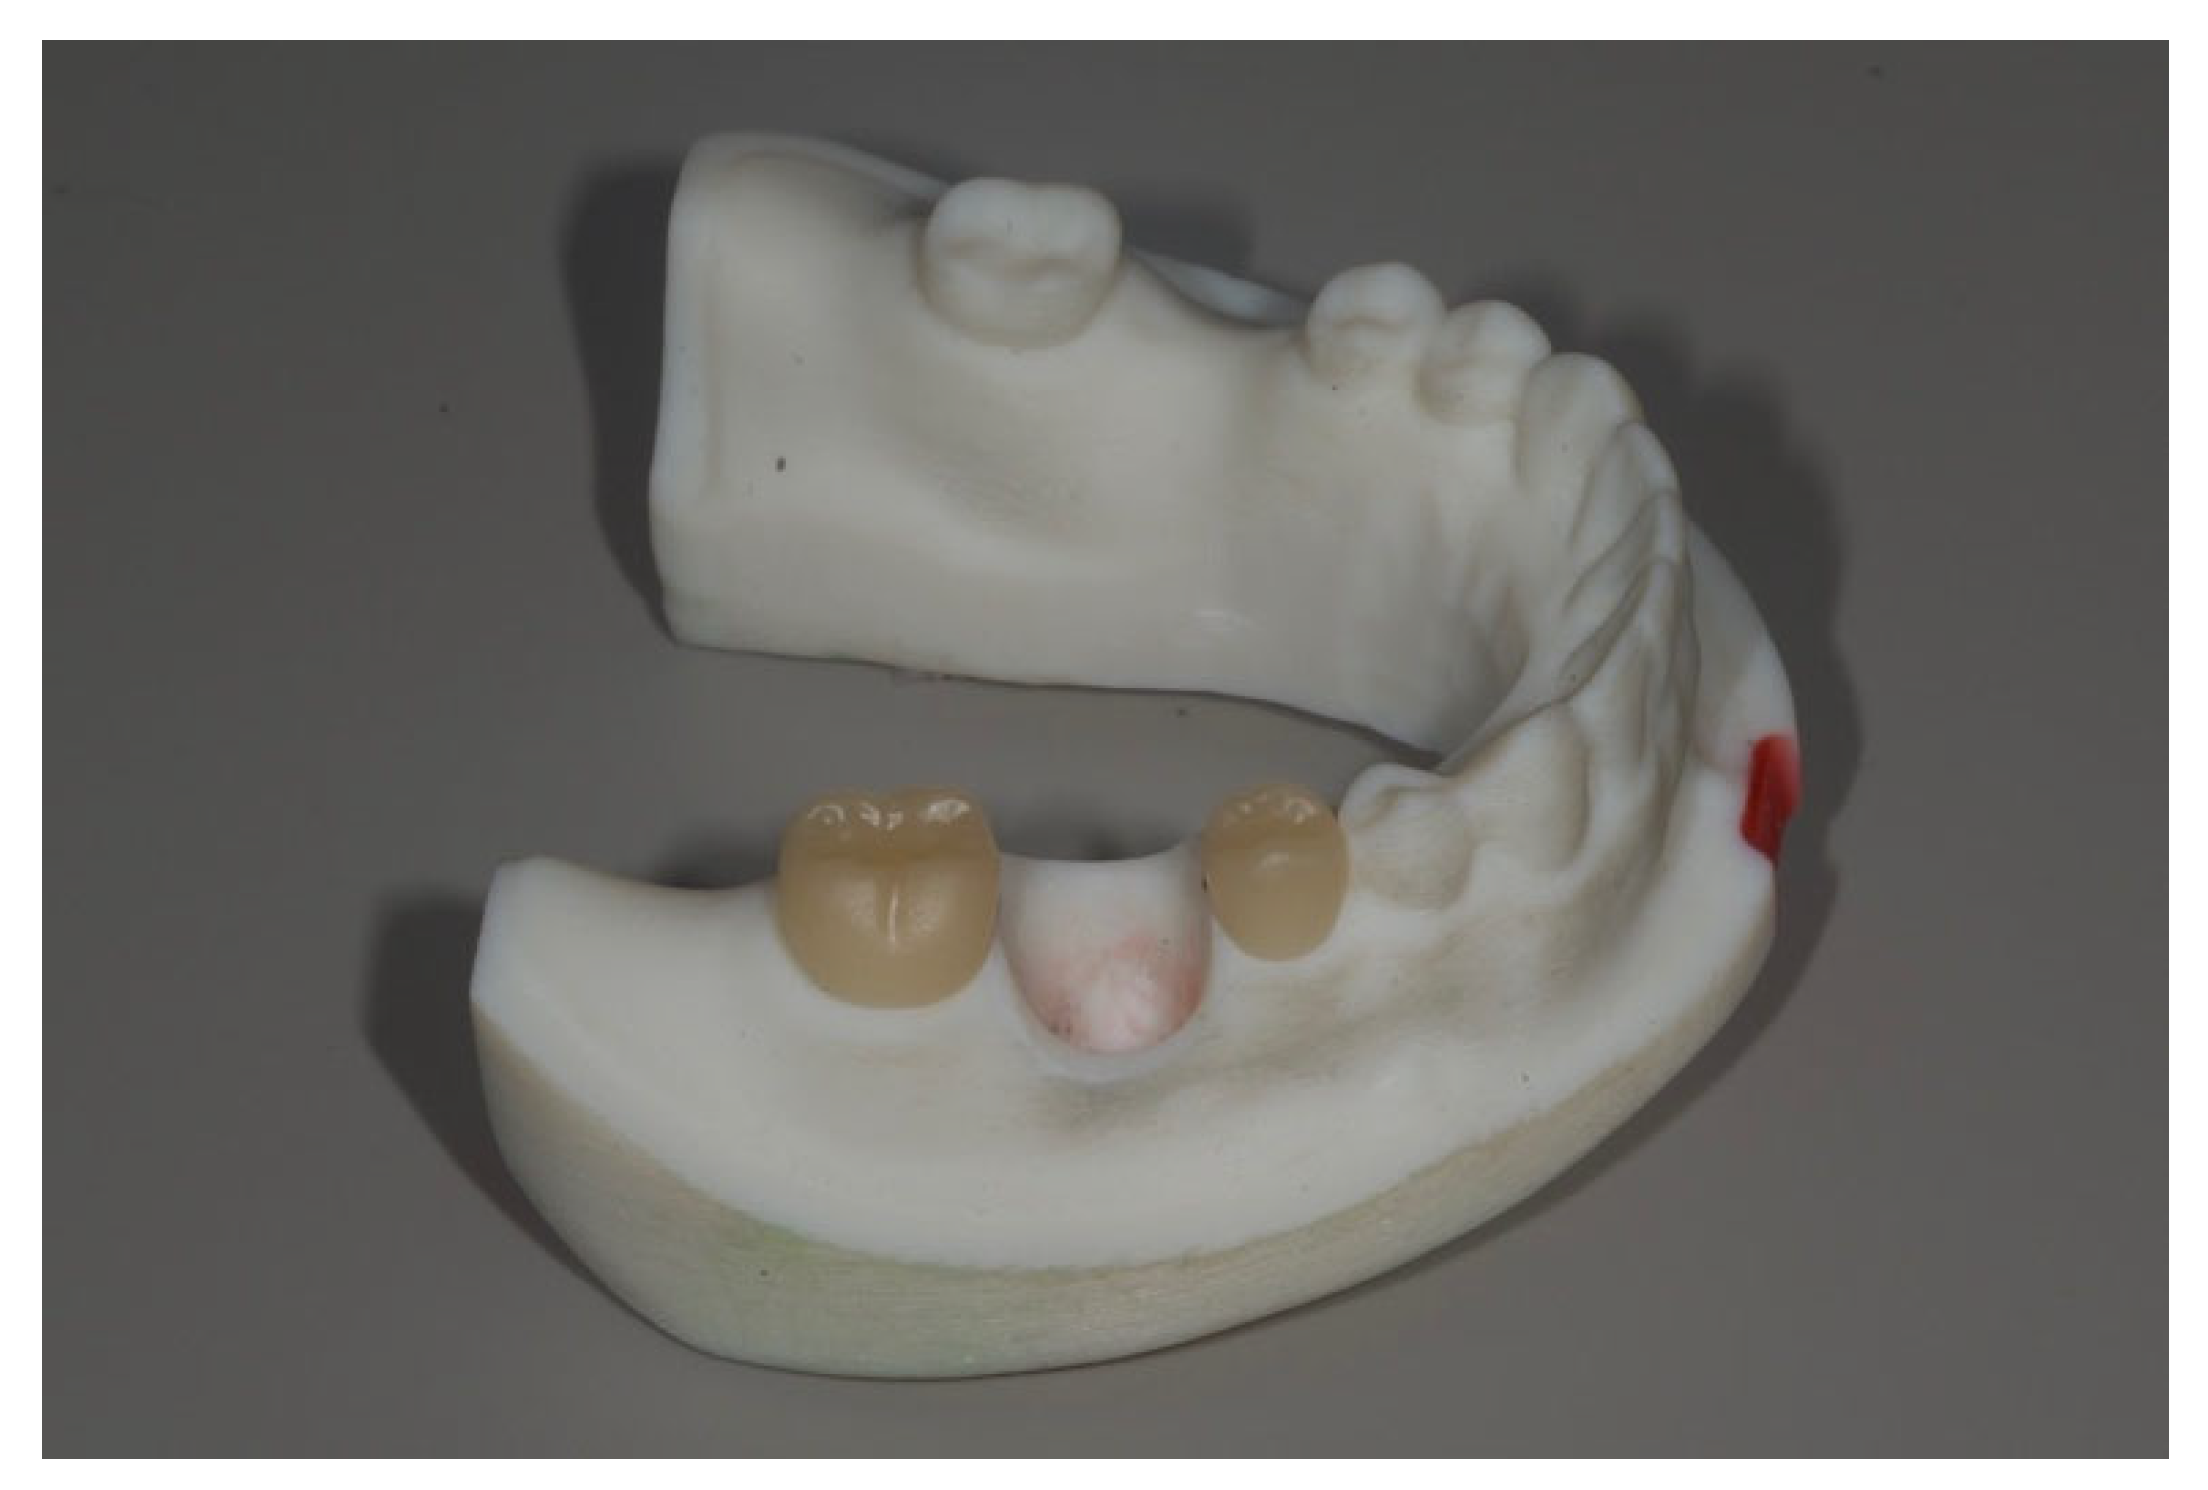

Each interchangeable implant die with its corresponding abutment was then sequentially positioned into the master model′s implant recipient site. Implant-supported crowns were fabricated following the same design and milling protocol used for the adjacent crowns. This process was repeated for all five implant dies, resulting in five implant-supported restorations, each corresponding to one of the experimental groups (Figure 3).

Figure 3.

Three kinds of removable dies with an implant and its corresponding CAD-CAM abutment were placed into the recipient sites. From left to right, Group Cent, Group L10, Group L15.